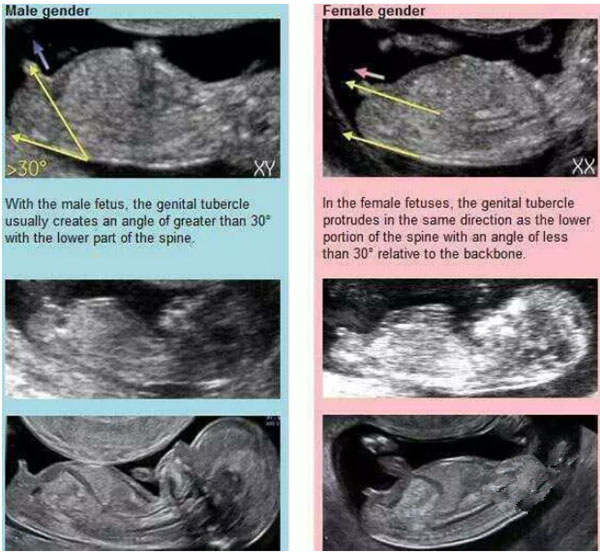

NT看男孩女孩,主要通过胎儿尾椎处判断。男胎儿,生殖部位和脊柱的下部通常会产生大于30的角;女胎儿,生殖部位在脊柱的下端向同一个方向突出,相对脊椎会形成小于30度的角。